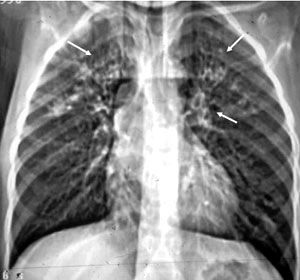

1. Radiografía de tórax